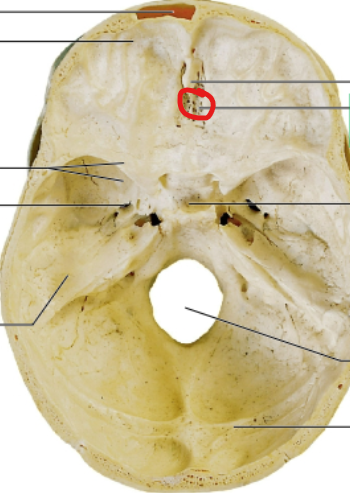

sella turcica

pituitary gland sits here

cribriform plate

olfactory nerves sits here